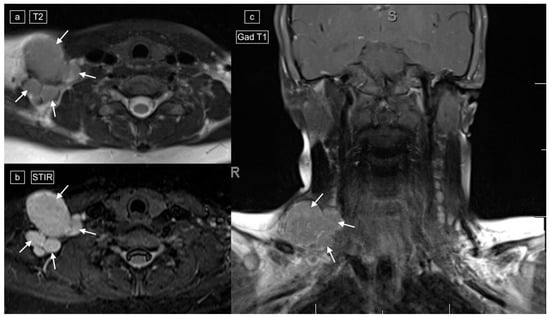

Figure 4.

Images demonstrating technical reasons for lower T2 signal of lymphadenopathy. MRI of the cervical region in a 12-year-old male with a histologic diagnosis of nodular sclerosing Hodgkin lymphoma. The right lower cervical lymphadenopathy (arrows) demonstrates low signal on T2 (a) and higher signal on STIR (b), with only mild enhancement on post-gadolinium T1-weighted imaging (c).